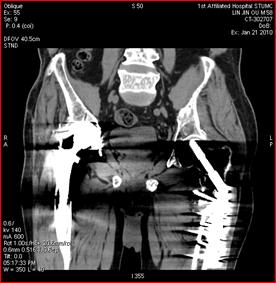

高能量X射線可以去除高密度金屬引起的偽影

常規(guī)CT 寶石能譜CT

140keV能量成像可以除去金屬引起的偽影,更加清晰觀察術(shù)后情況